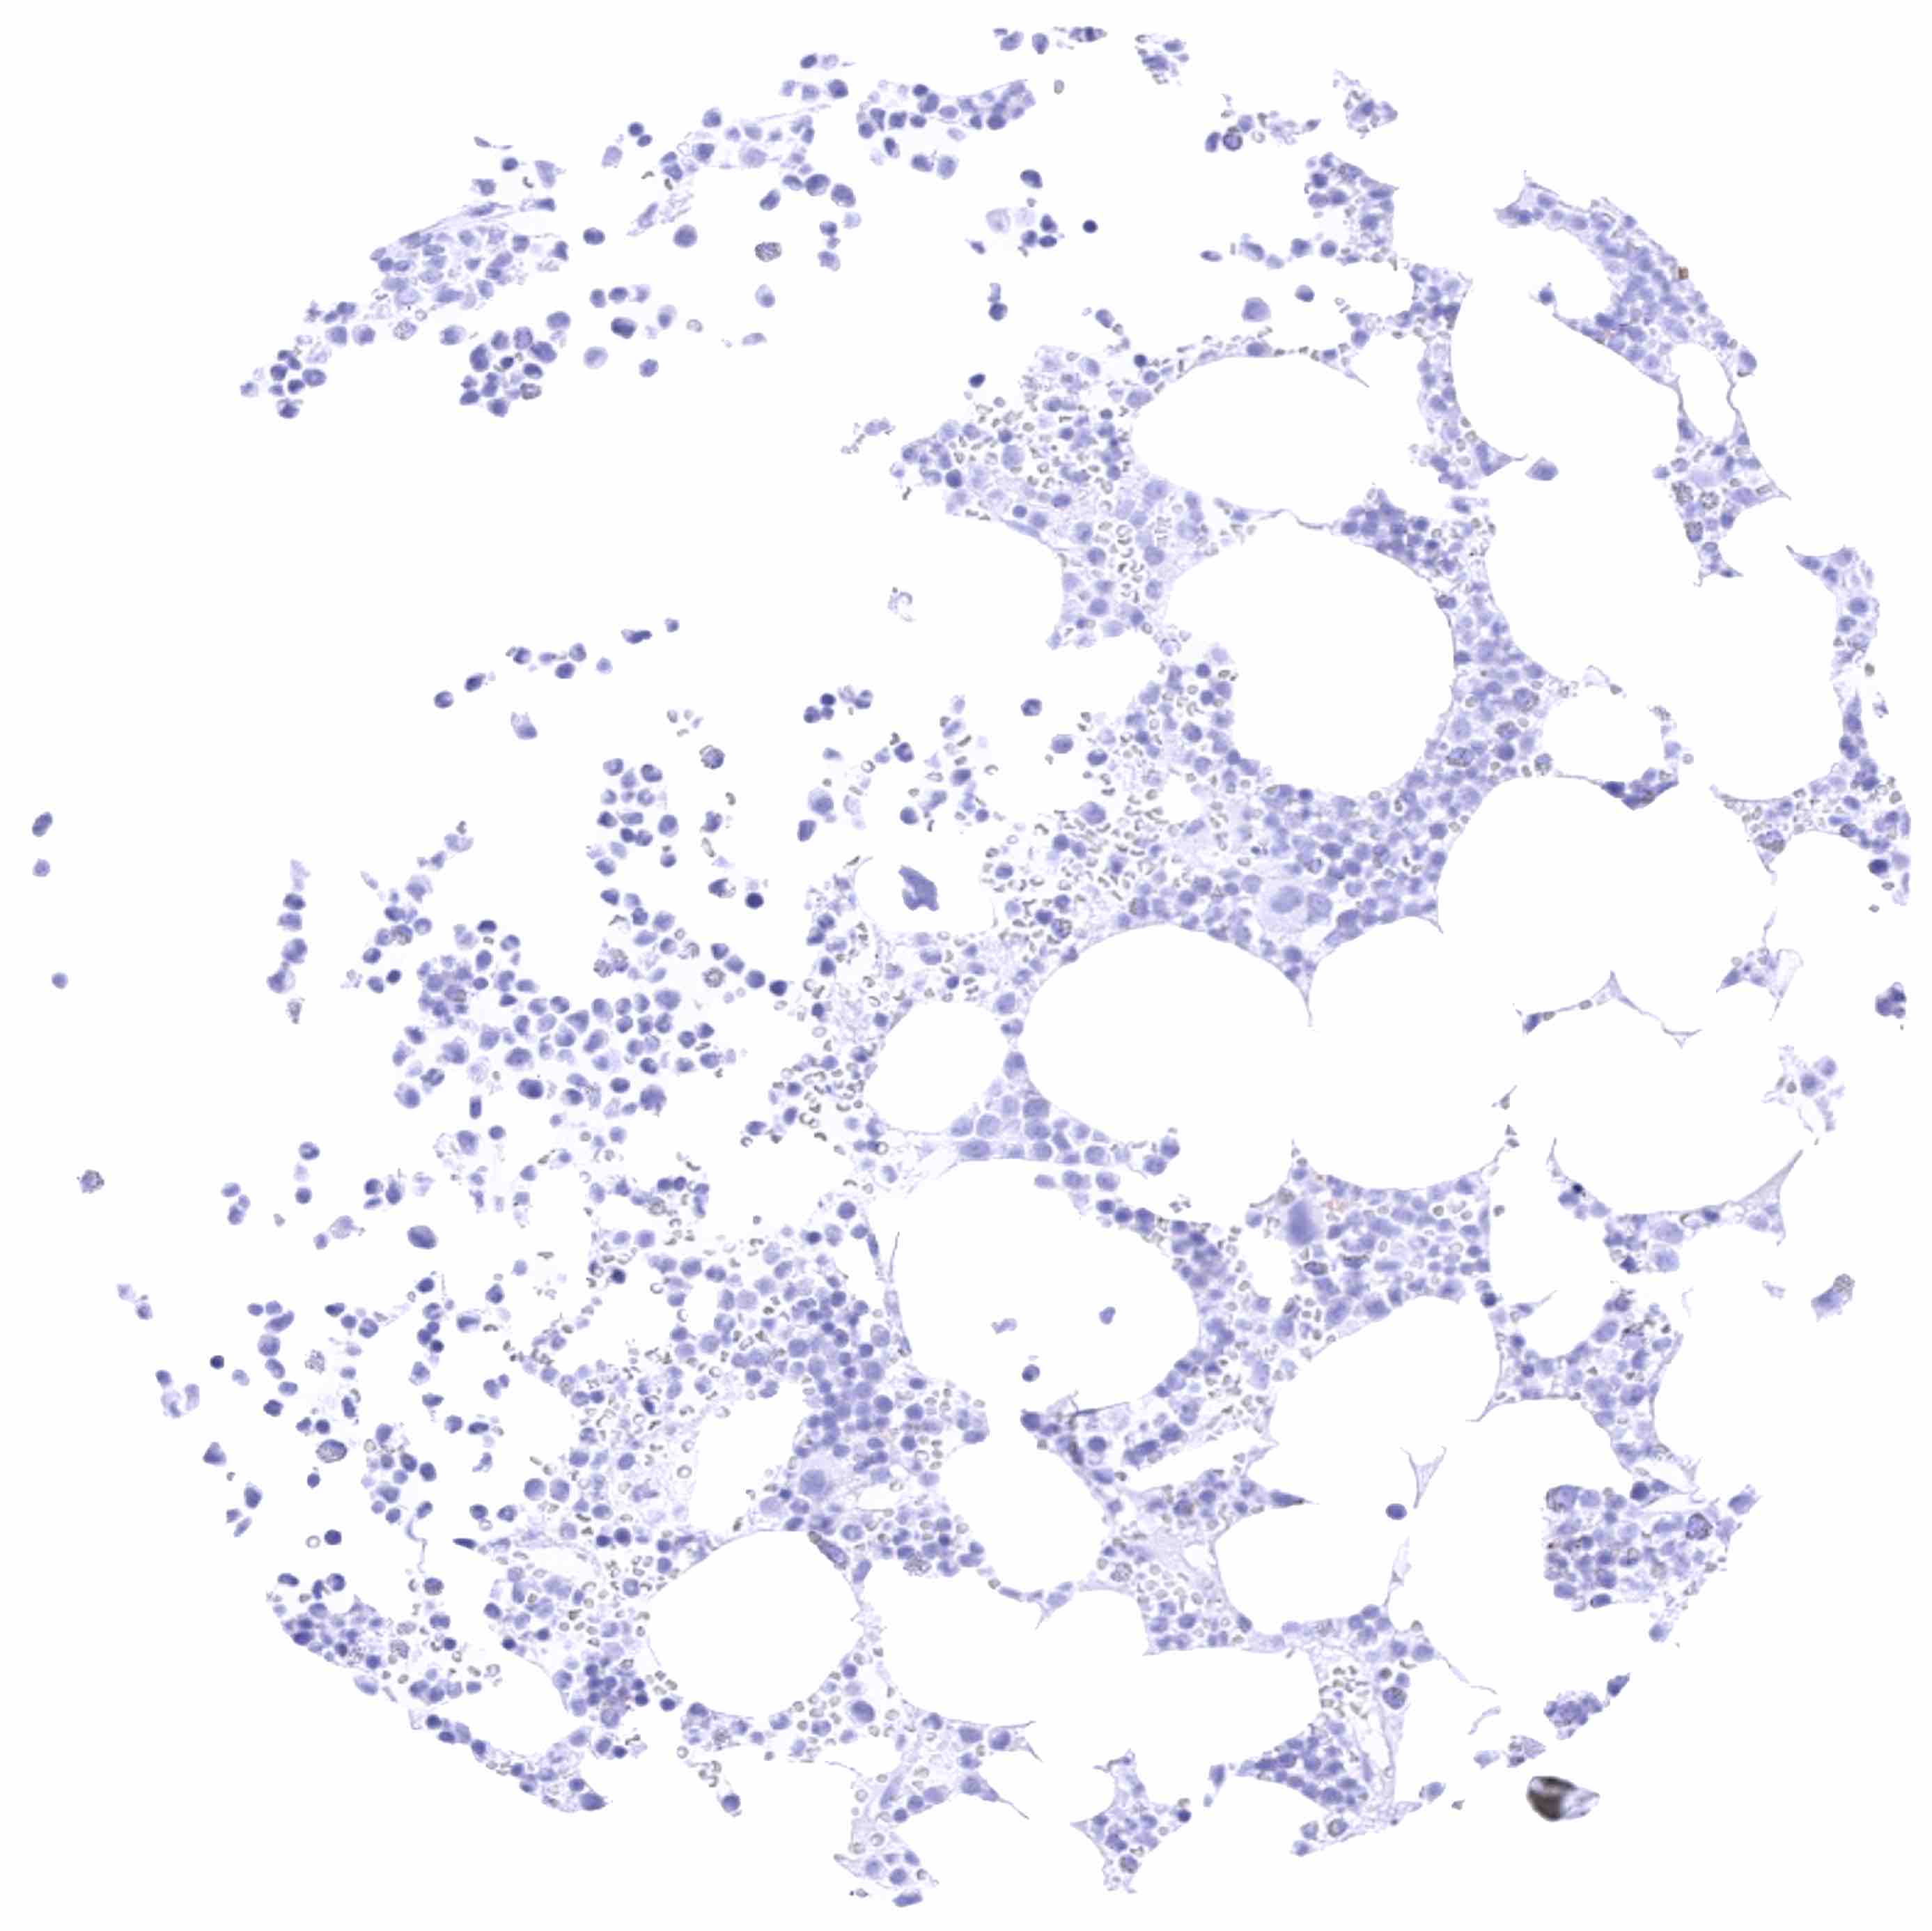

Bone marrow